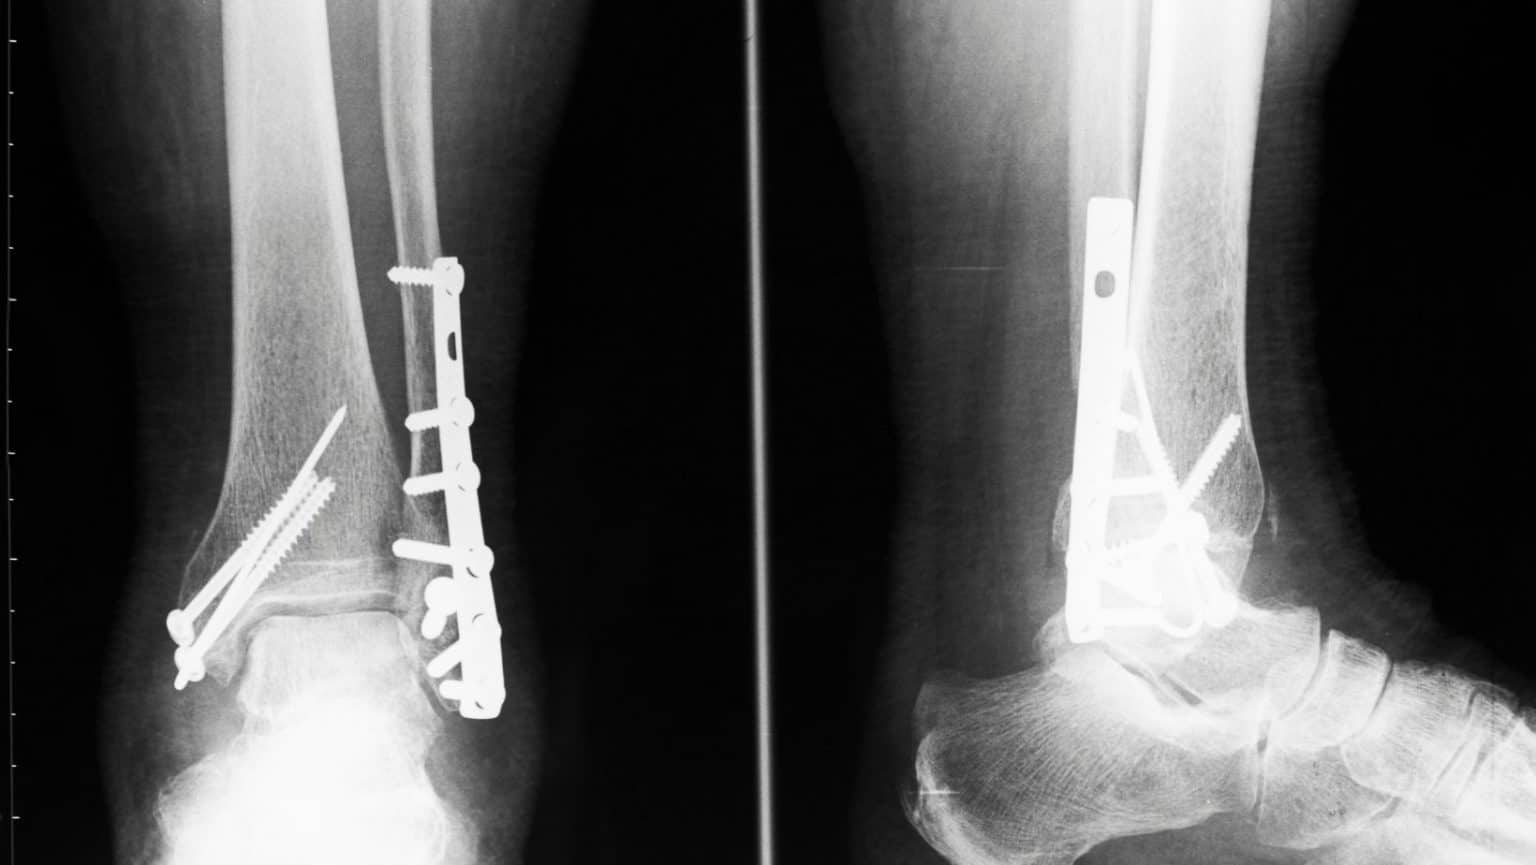

Treatment Of Medial Malleolus Fracture OrthoFixar 2024 Medial Malleolus Fracture Walking Boot In rare cases, if the bone fragment and main bone are too far apart to fuse naturally, surgery may be needed to reunite them. Patients with a medial malleolus fracture typically experience a sudden onset of sharp, intense inner ankle or lower leg pain at the time of injury. Do not place ice in. Avulsed bone fragments can be put. Medial Malleolus Fracture Walking Boot.

Single Oblique Posterolateral Approach for Open Reduction and Internal Medial Malleolus Fracture Walking Boot An isolated fracture or break of the medial malleolus is rare and often occurs in combination with a break or fracture of the fibula, the long thin bone on the outside of the ankle. If you are unable to bear weight and. Fractures of the ankle joint are common amongst adults. In rare cases, if the bone fragment and main. Medial Malleolus Fracture Walking Boot.